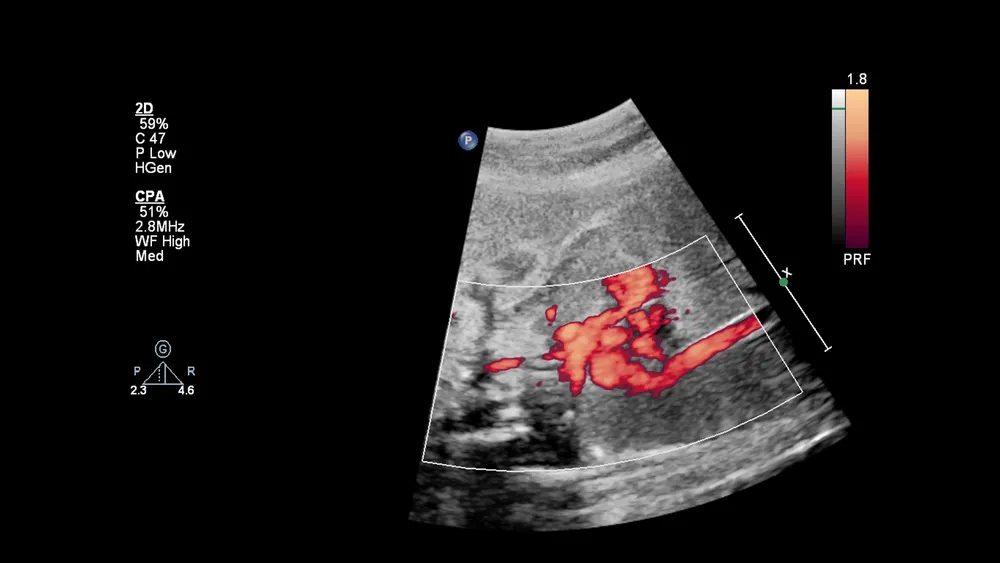

דוגמה לאקו לב עובר ( תמונה למאמר)

בדיקת אקו לב עובר מתבצעת על-ידי קרדיולוג ילדים באמצעות מכשיר אולטרסאונד מתקדם והיא אינה מצריכה כל הכנה מוקדמת. ברוב המקרים, הבדיקה תתבצע בגישה בטנית, אך אם היא נדרשת בשלבי הריון מוקדמים יותר ייתכן שתתבצע בגישה וגינלית (בשיתוף עם רופא נשים). בשונה מבדיקת סקירת מערכות בה נבחנות כלל מערכות הגוף של העובר, בדיקת אקו לב עובר מתמקדת בלב עצמו, בכלי הדם המזינים אותו ובאלו היוצאים ממנו במטרה לבחון את תפקוד המערכת הליבית בלבד. תוצאות הבדיקה נמסרות מיד בתום הבדיקה על-ידי קרדיולוג ילדים, בו ינתן  הסבר מפורט על הממצאים, הנחייה בנוגע לבדיקות נוספות אם נדרשות (למשל ייעוץ גנטי או ביצוע של בדיקת מי שפיר) וגם משמעויות אפשריות של המום במידה והתגלה.